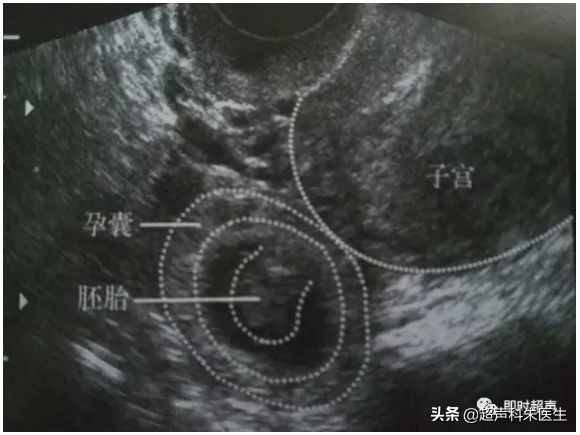

正常早孕:宫腔内见到低回声的孕囊,其内见到卵黄囊,甚至是胚芽,可见原始心管搏动。

正常早孕

①先兆流产 :妊娠囊的大小与妊娠周数相符,子宫壁与胎膜间出现新月形无回声区,胎芽或胎儿及胎心无超声可发现的异常。